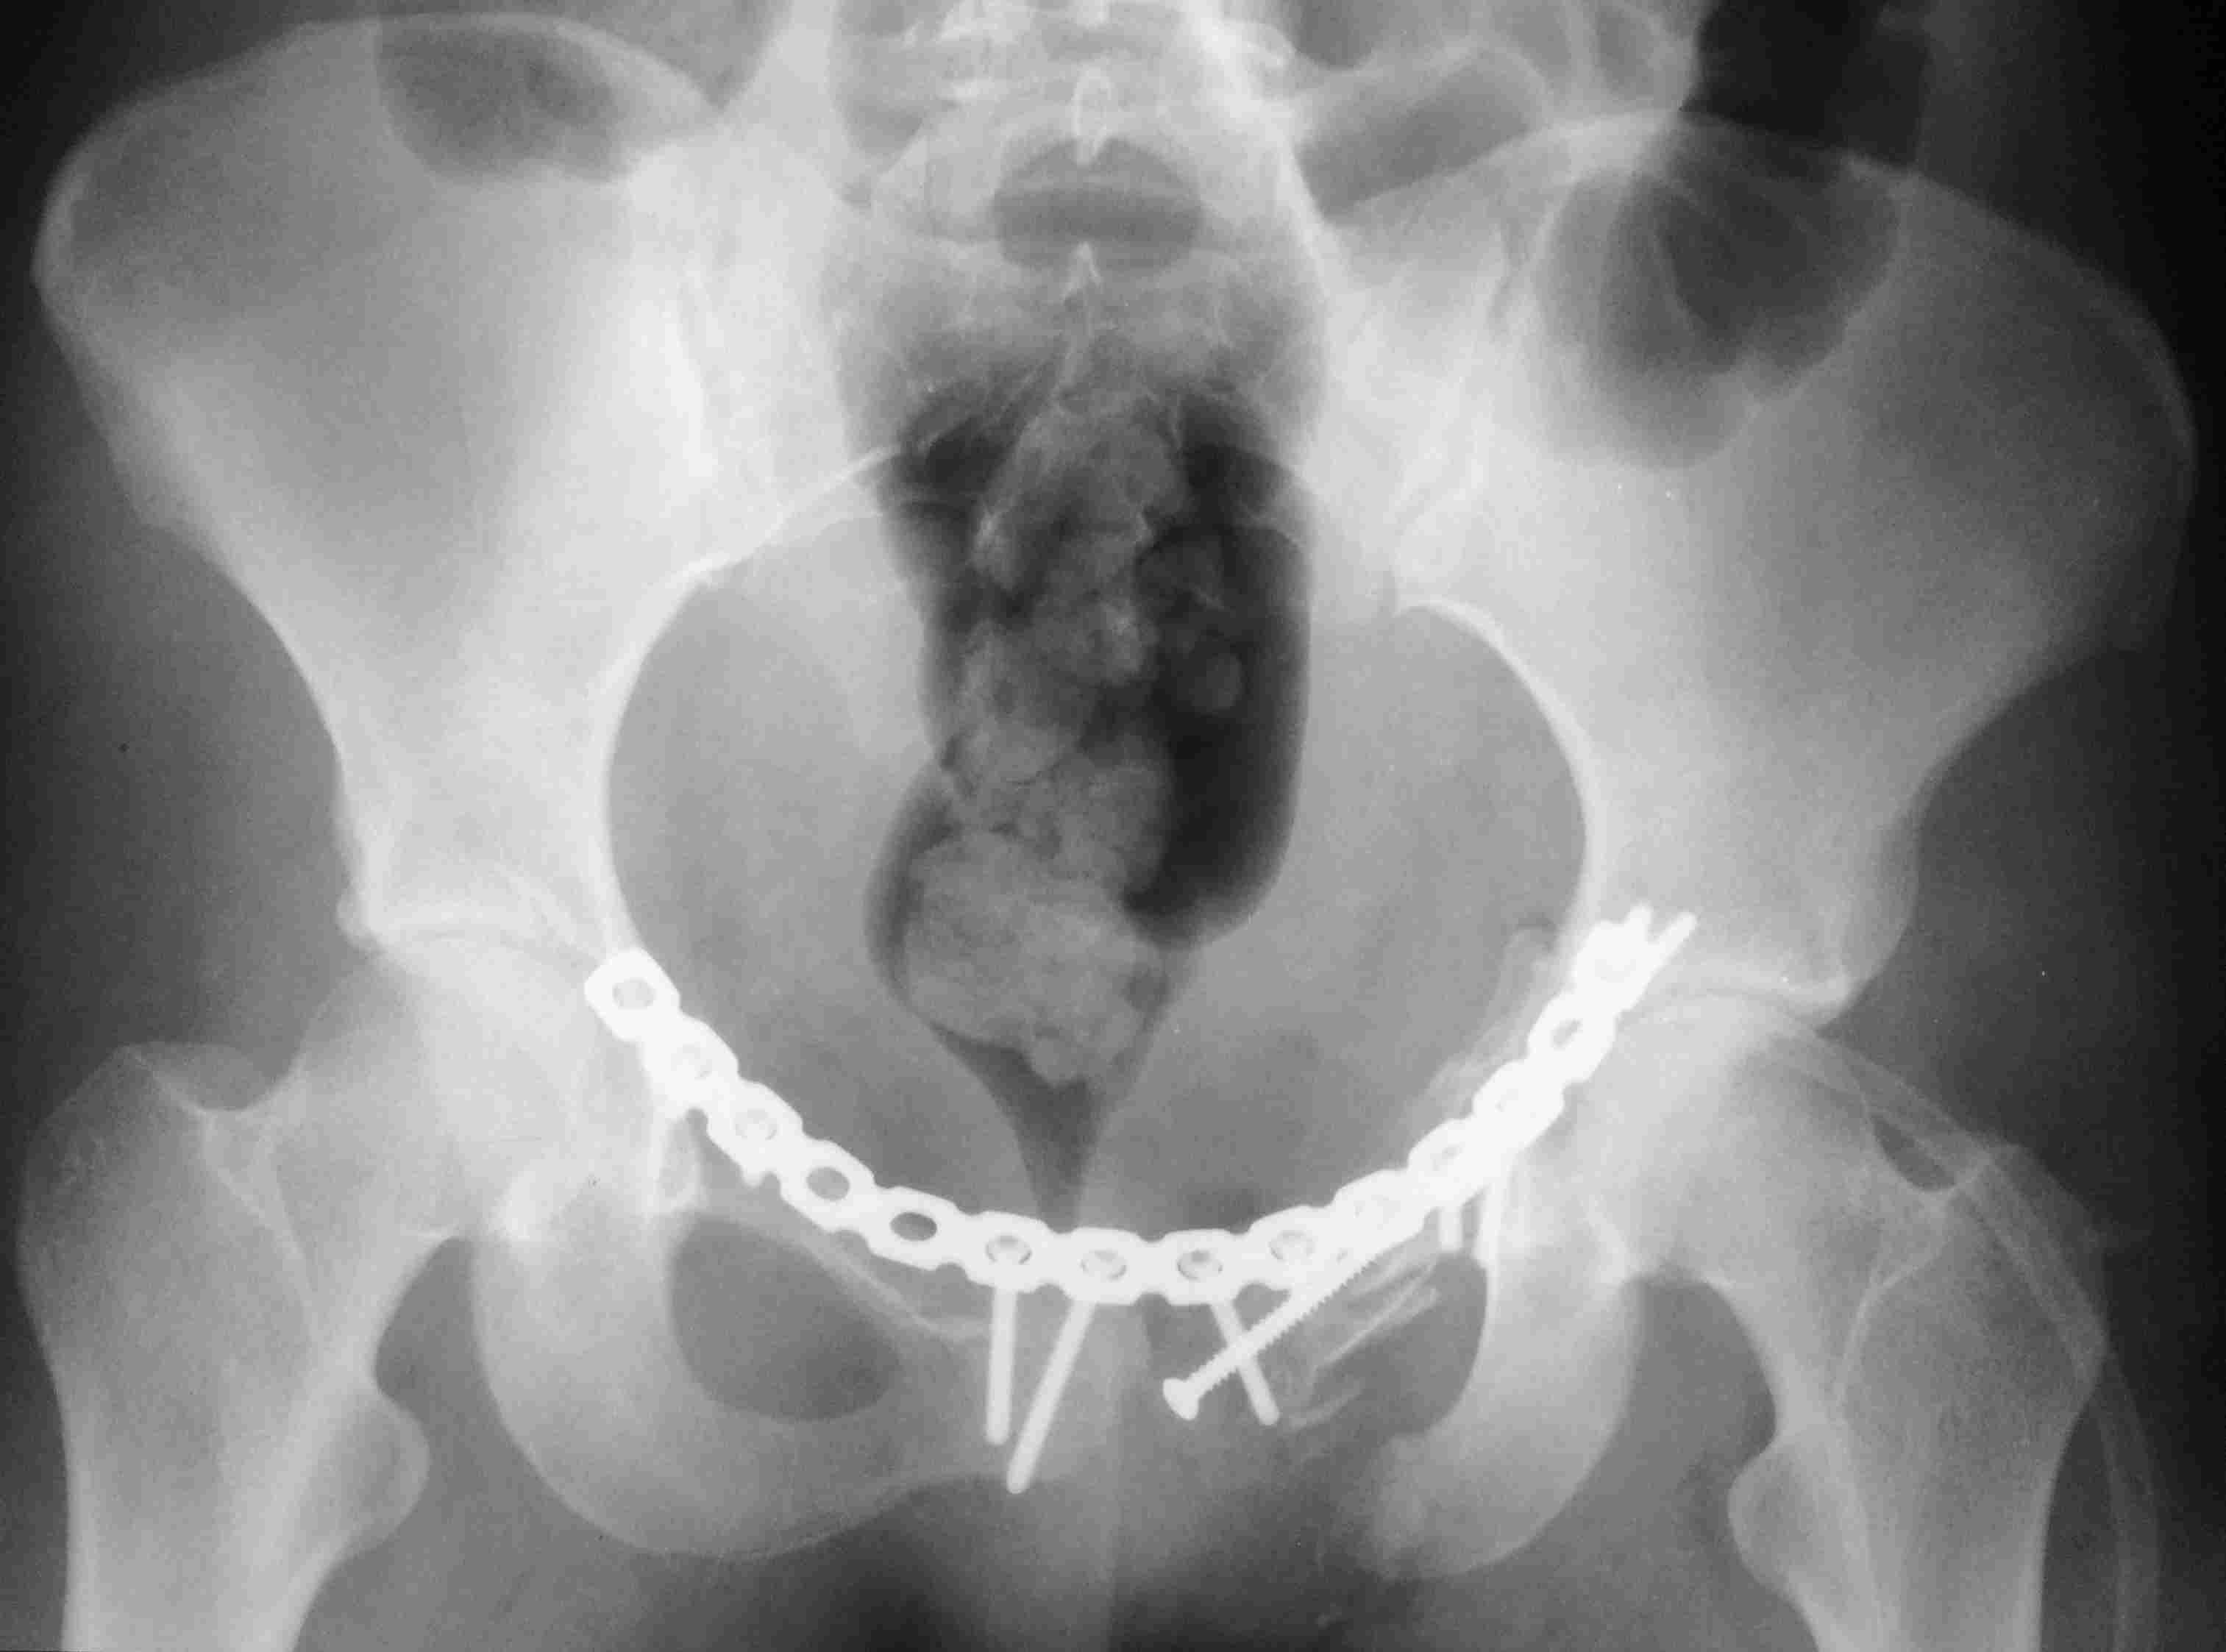

[Ortho] повреждение таза с необычным смещением

Постоп. Верхняя ветвь возле шейки мочевого пузыря, нижняя так же где-то

глубоко в мышцах, ротирована. Обе практически лишены кровоснабжения.

лонное сочленение фактически свободно лежащее, справа  почти целое, но

ветви сломаны возле него. Слева часть лонного сочленения цела на 2/3.

интраоперационно подвижность правой половины таза. Постоп все стабильно,

но все же планирую дополнительно провести IS винт справа.